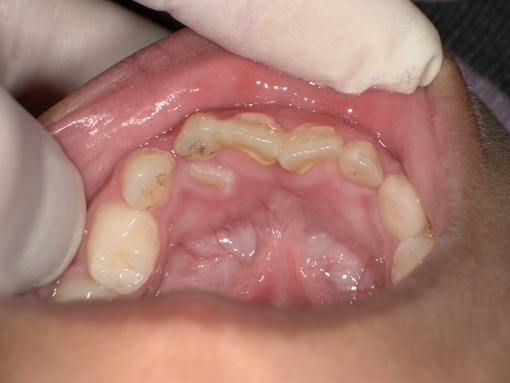

永久歯の舌側転位 乳歯の抜歯前 Before

拝見したところ、右上の前歯は永久歯が生えてきているのにも関わらず、乳歯(乳犬歯)が抜けずに口腔内に残っている「乳歯晩期残存」が認められました。

このまま放置すると、乳歯と永久歯の間に汚れが溜まりやすくなり、歯茎が炎症を起こす「歯肉炎」のリスクが高まります。

また、乳歯が残ったままだと永久歯が生える十分なスペースを確保できず、その状態で永久歯が無理に生えてきてしまうと、将来的に歯並びや噛み合わせに悪影響を及ぼすおそれもあります。

以上のことから、残存している乳歯を抜いて、永久歯が正しく生えるためのスペースを確保する必要があると診断しました。